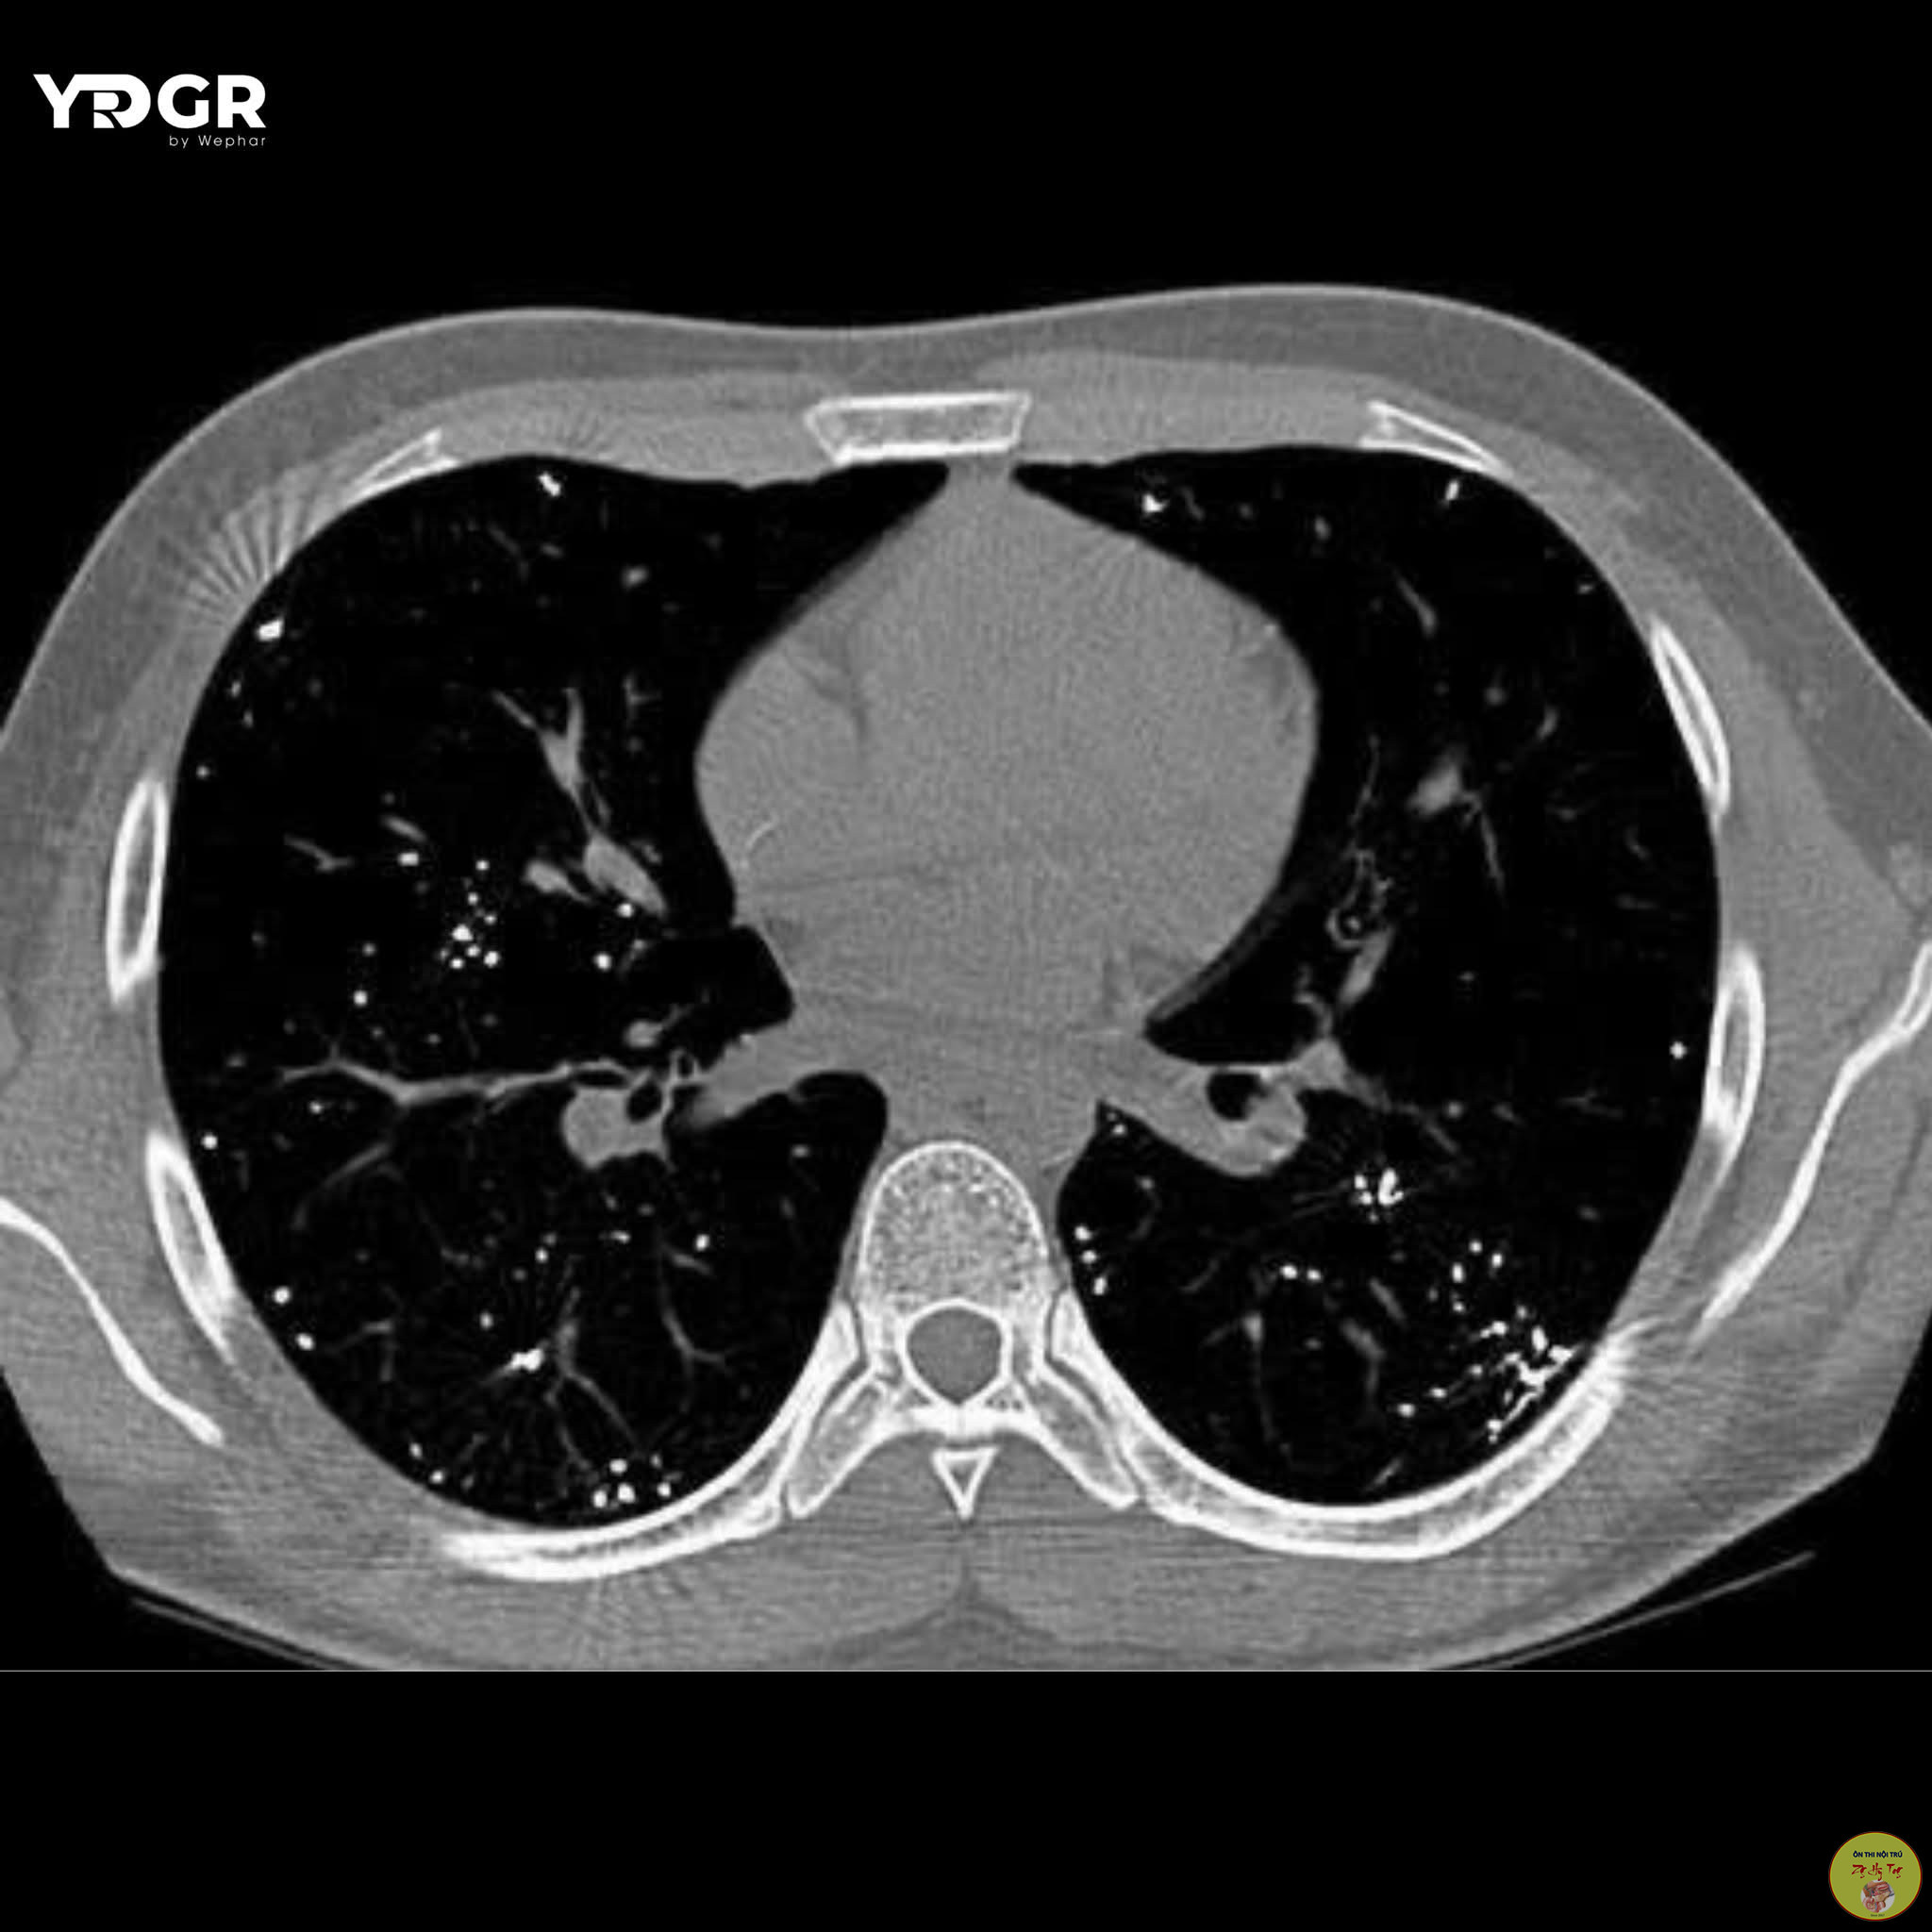

Ca lâm sàng thực tế, vận dụng lý thuyết bệnh học